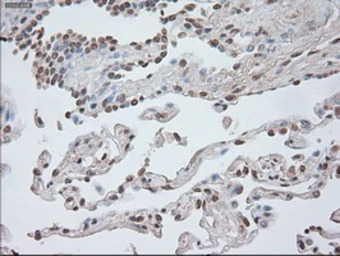

IHC-P analysis of human lung tissue using GTX84650 beta Catenin antibody [1F3].

Antigen retrieval : Heat-induced epitope retrieval by 10mM citrate buffer, pH6.0, 100ºC for 10min.